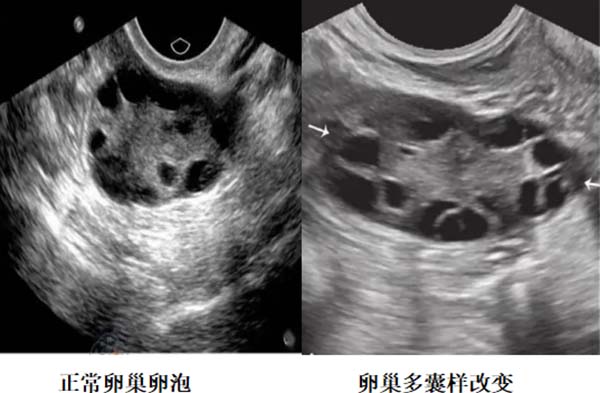

更令人担忧的是,青春期PCOS的诊断难度更高。由于青春期女孩的下丘脑-垂体-卵巢轴尚未成熟,激素水平波动大,单纯的“卵巢多囊样改变”并不等于PCOS——很多健康女孩的B超也可能显示卵巢有多囊,但只要月经规律、无胰岛素抵抗,可暂观察,但需要警惕。

因此,诊断青春期PCOS必须“多指标综合判断”,除子宫附件B超,还要结合性激素六项(重点看睾酮、LH/FSH比值)、抗苗勒氏管激素(AMH,反映卵巢储备)、胰岛素释放试验等,缺一不可。